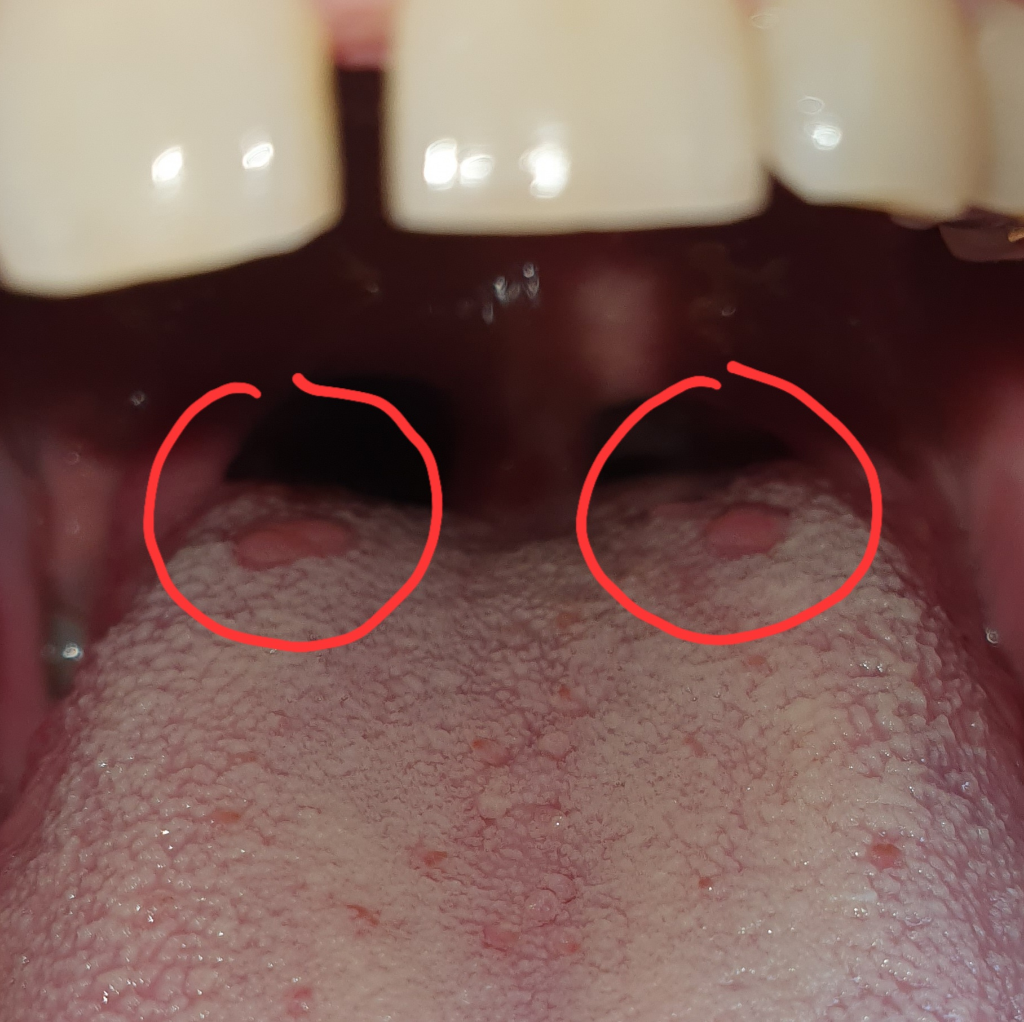

혀 안쪽 끝을 보니 돌기 같은게 보이는데 혹시 설암 일까요?

양치하다 우연히 혀 안쪽 뿌리쪽을 봤는데 돌기? 종양? 같은게 보여 혹시나 종양이나 암의 증상이 아닌가 싶어 걱정이 됩니다

의사 선생님들의 고견 부탁 드리겠습니다

정상적인 혀의 유두돌기가 보이는 겁니다. 설암은 아니구요. 혹시 흡연자시라면 늘 암에 대한 염려가 가득하니 금연을 권합니다.